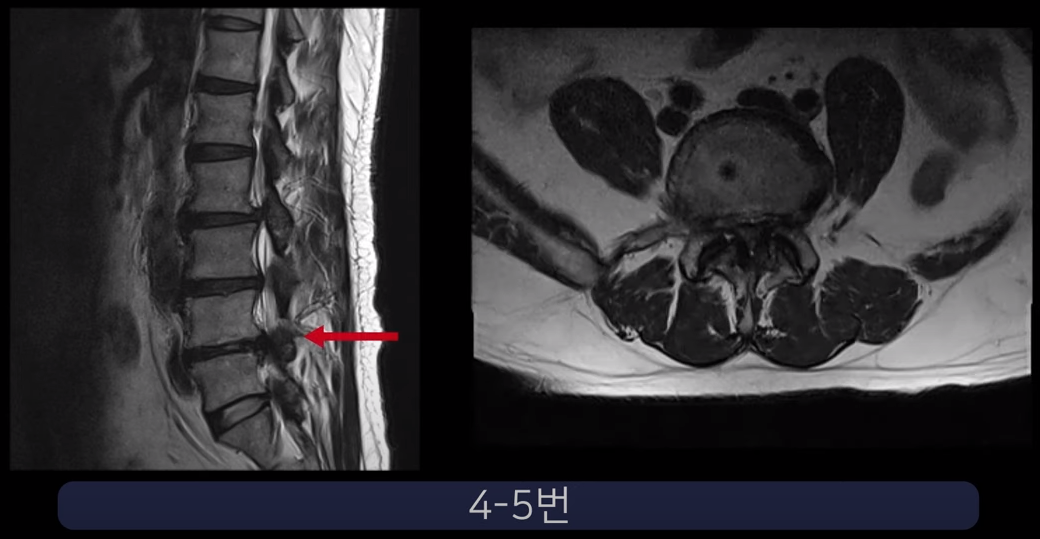

실제 척추관과 추간공이 심하게 막힌 두 환자 케이스를 보여드리겠습니다.

첫 번째 환자분입니다. 이 환자분은 허리 세 마디에 심한 협착이 있습니다. 2-3번, 3-4번, 4-5번 이렇게 척추관이 세 마디가 심하게 막혀있습니다.